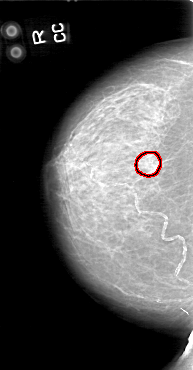

D_4044_1.RIGHT_CC

FILE: D_4044_1.RIGHT_CC.OVERLAY

TOTAL_ABNORMALITIES 1

ABNORMALITY 1

LESION_TYPE CALCIFICATION TYPE COARSE DISTRIBUTION CLUSTERED

ASSESSMENT 0

SUBTLETY 5

PATHOLOGY BENIGN

TOTAL_OUTLINES 2

BOUNDARY